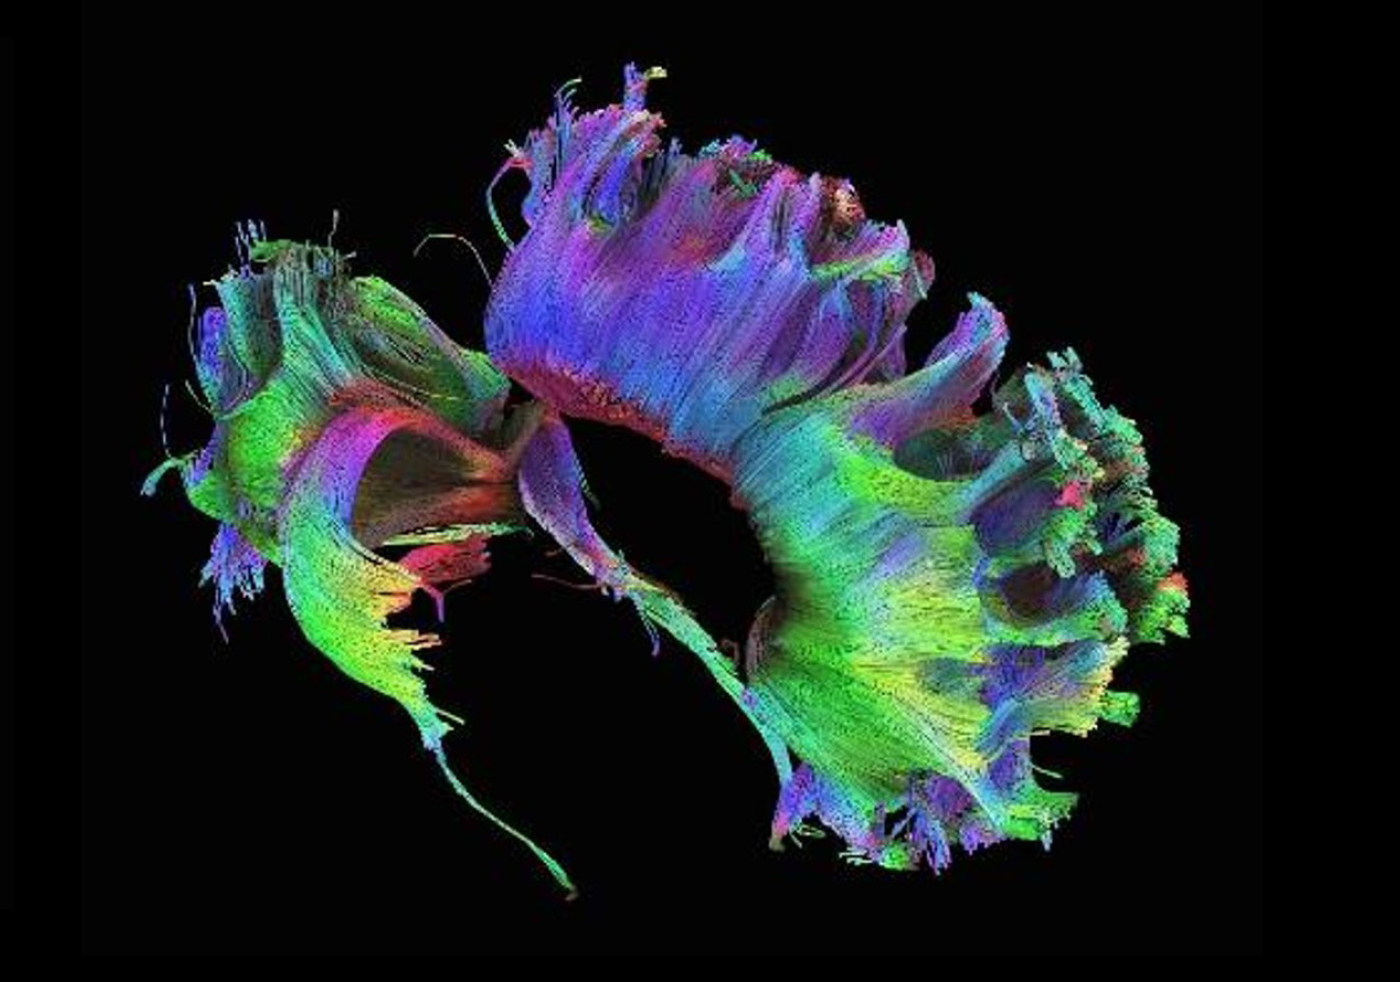

High angular diffusion imaging

The neuroscience team used 257 different directions, 23 b-values and a maximum b-value of 4000 s/mm² to collect the data below in a total scan time of 11 minutes. The higher number of gradient directions combined with multiple b-values not only allows for improved fiber tracking in these examples, but also enhances the analysis of intra-voxel incoherent motion (IVIM) and diffusion kurtosis (DK) effects in one single measurement.

High angular diffusion imaging

The neuroscience team used 257 different directions, 23 b-values and a maximum b-value of 4000 s/mm² to collect the data below in a total scan time of 11 minutes. The higher number of gradient directions combined with multiple b-values not only allows for improved fiber tracking in these examples, but also enhances the analysis of intra-voxel incoherent motion (IVIM) and diffusion kurtosis (DK) effects in one single measurement.